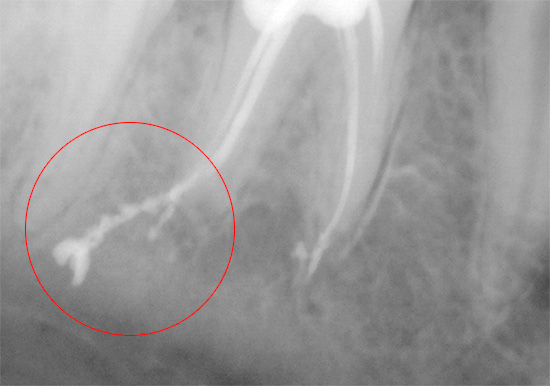

Por exemplo, os erros mais comuns no tratamento da pulpite fibrosa são o preenchimento insuficiente dos canais dentários. O padrão de qualidade para o tratamento de canais permite o preenchimento de todo o comprimento com firmeza e o ápice - constrição fisiológica. Se o canal não estiver selado na marca indicada, no futuro poderá haver grandes problemas associados à ativação da infecção nos vazios do canal. É especialmente perigoso quando o canal é apenas 20-50% selado.

É mais difícil corrigir o erro associado à remoção do preenchimento de material intracanal além da raiz.Às vezes, esse erro vale a saúde do paciente se o material penetrar profundamente no seio maxilar (ao tratar os canais do dente superior) ou no canal mandibular (ao tratar o dente inferior).

Nesses casos, o material de enchimento removido atua como um corpo estranho, irritando os tecidos e provocando fortes dores. A sinusite se desenvolve no seio maxilar e a neurite no canal maxilar. A ajuda oportuna na forma de intervenção cirúrgica por um dentista-cirurgião para extrair o excesso de material economiza saúde e, muitas vezes, vida ao paciente. Por razões óbvias, um dente com essa complicação geralmente precisa ser removido para fornecer melhor acesso a materiais estranhos.